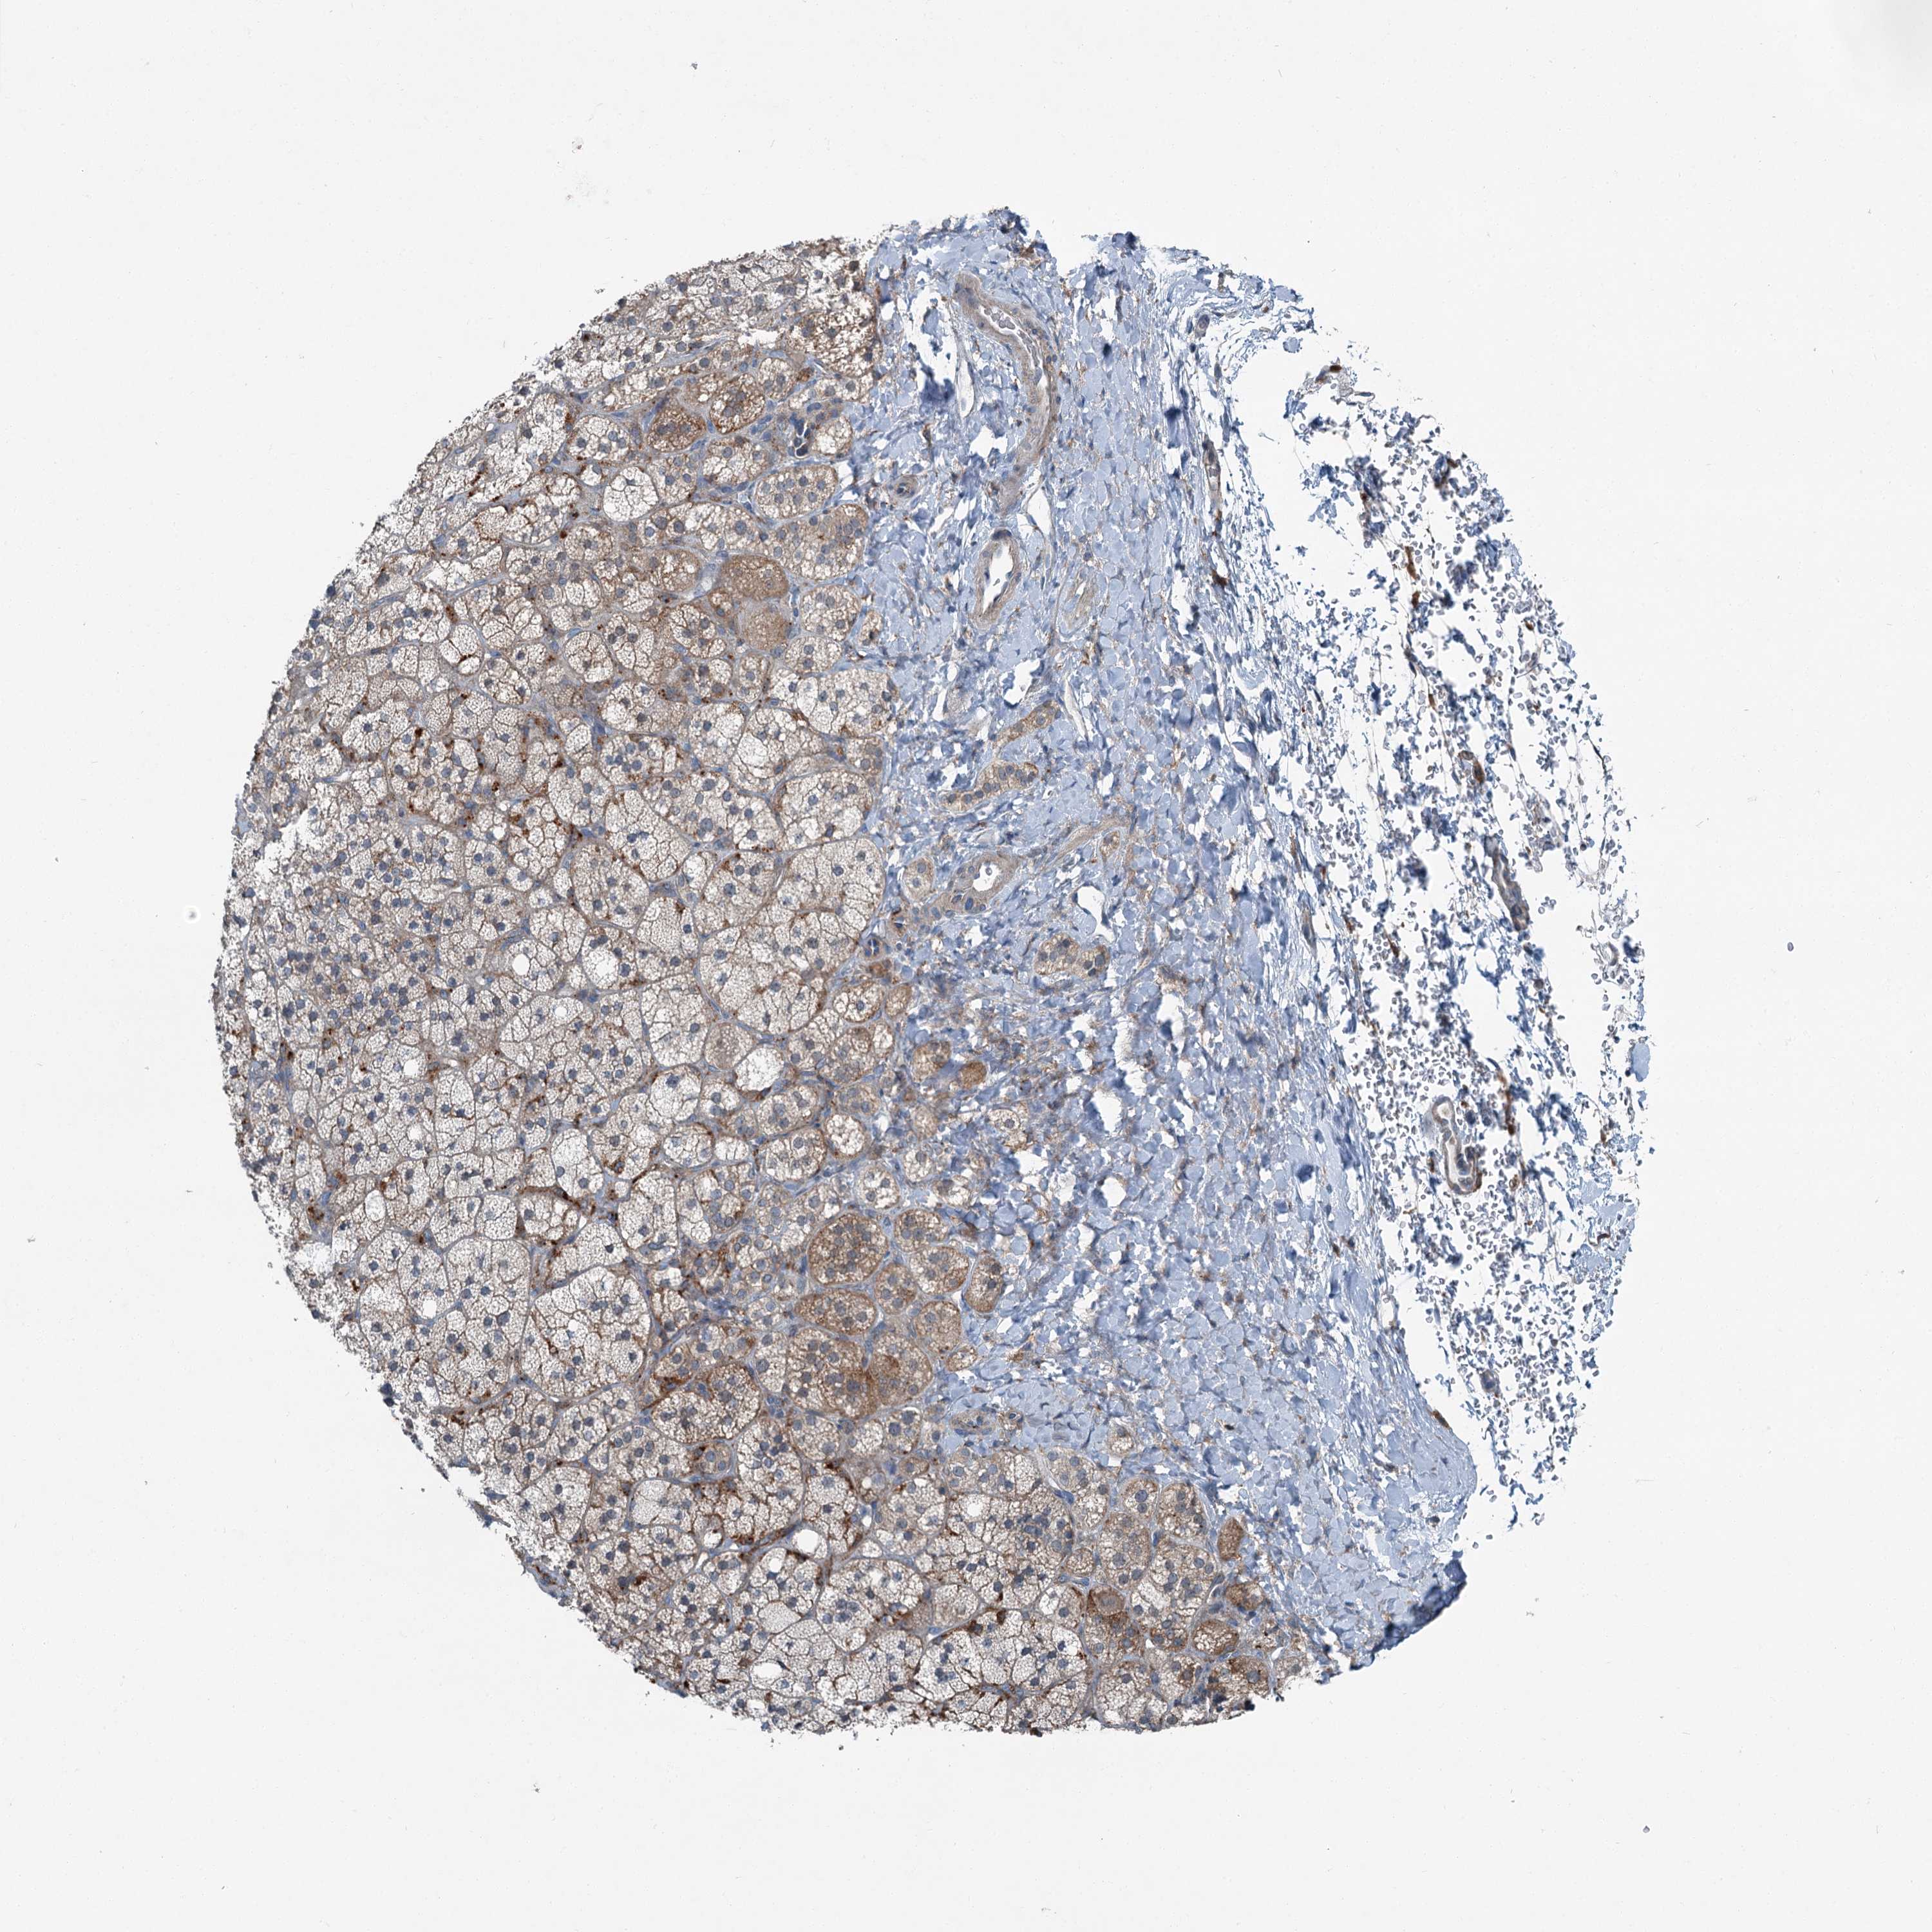

ADRENAL GLAND - Antibody stainingi

Antibody staining in the annotated cell types in the current human tissue is reported as not detected, low, medium, or high, based on conventional immunohistochemistry profiling in selected tissues. This score is based on the combination of the staining intensity and fraction of stained cells.

Each image is clickable and will lead to virtual microscopy that enables deeper exploration of all samples and also displays staining intensity scores, fraction scores and subcellular localization as well as patient and tissue information for each sample.

Antibody HPA037422Antibody HPA037423Antibody CAB032501

Glandular cells Not detectedNot detectedMedium